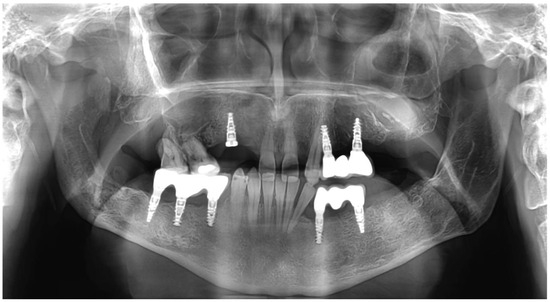

In this patient, multiple cystic lesions were accidentally detected in both the mandible and the maxilla through dental X-rays (Figure 1).

The intraoral examination revealed poor oral hygiene, with periodontitis, several missing teeth, and a few persistent roots. No visible manifestations of the cystic lesions in the oral cavity were detected. Panoramic radiographs and a CBCT scan revealed four cysts in both the mandible and maxilla (Figure 2). The first extensive radiolucent lesion spanned the right mandible from the condyle to the angle. A second, two-chamber osteolytic lesion was located in the right mandibular body in the molar area. Diagnostic imaging also revealed two cystic lesions in the left mandibular body in the premolar area and another in the maxilla, which was located between teeth 24 and 26 and was pushing their roots away from each other. The preparation for surgery consisted of scaling, a periodontic treatment, and dental sanation.

Figure 1. Preoperative X-rays: (a) residual roots and multiple keratocysts are visible on the orthopantomogram; (b) keratocysts are marked with yellow lines.